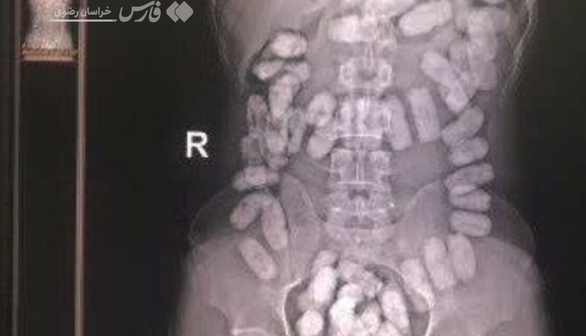

کشف ۳۳ بسته هروئین از معده یک تبعه خارجی در مرز تایباد

فارس/ فرمانده هنگ مرزی تایباد گفت: ۳۳ بسته مواد مخدر آب بندی شده با هوشیاری مرزبانان هنگ مرزی تایباد از معده یک تبعه خارجی کشف شد.

سرهنگ محمودی افزود: مرزبانان ایست و بازرسی ۱۷ شهریور حین بازدید و بازرسی مسافرین در لاین ورود به کشور موفق شدند، تعداد ۳۳ بسته مواد آب بندی شده به وزن ۳۷۲ گرم مواد مخدر از نوع هروئین که در معده جاساز شده بود را از یک تبعه افغان کشف کنند که مواد و متهم تحویل مراجع ذی الصلاح شدند.